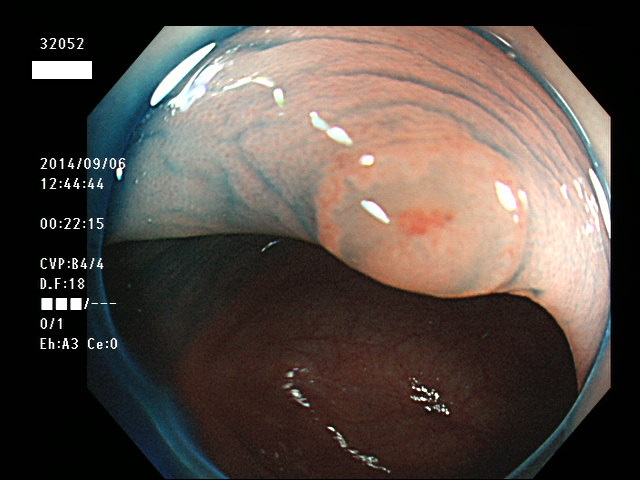

上記100名より抽出した平坦・陥凹型腺腫(=癌化の危険が高いが見落としやすい病変)の内視鏡写真